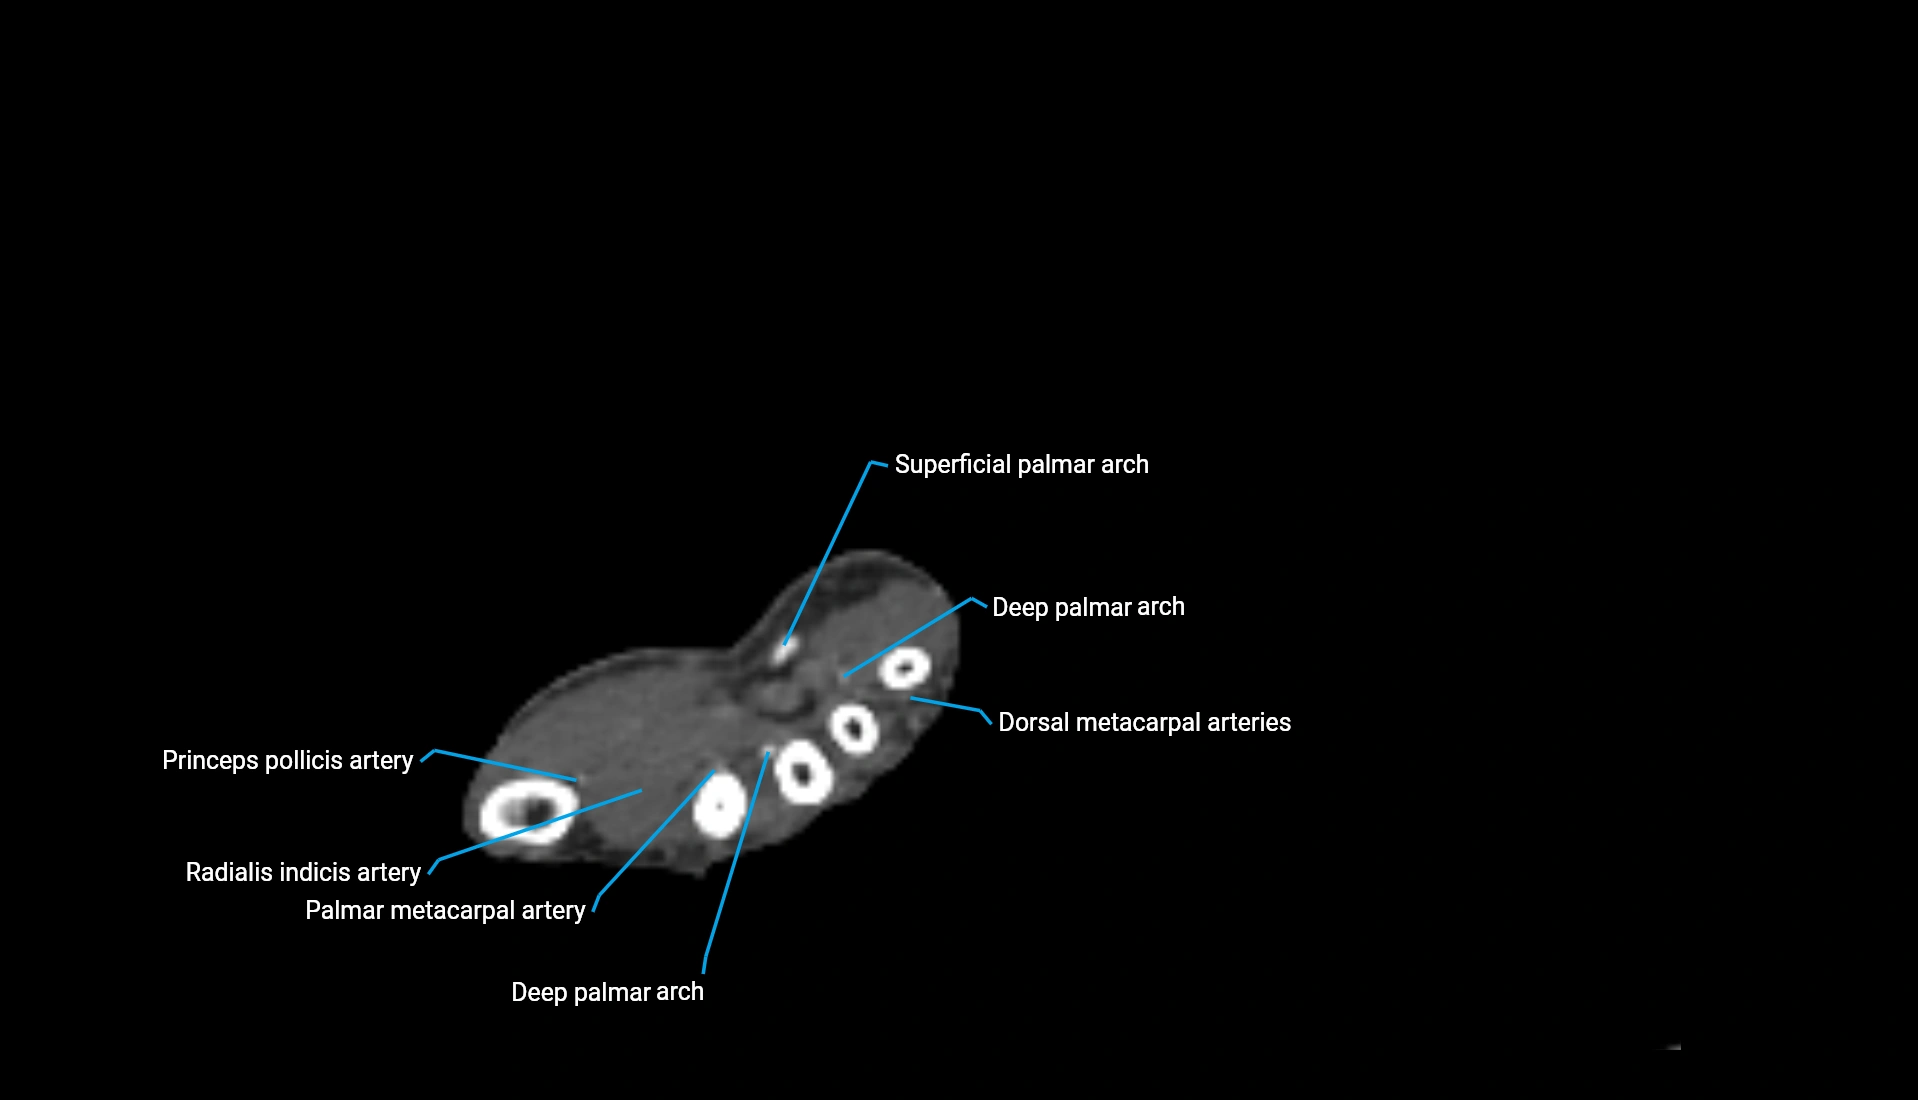

CT Appearance

Non-Contrast CT:

• Cortex: High-density, sharply defined

• Subchondral bone: Dense cancellous matrix

• Articular surface: Smooth concave contour articulating with the capitellum

• Excellent for evaluating bone integrity, alignment, and subtle fractures

Post-Contrast CT:

• Bone: No enhancement

• Joint capsule and synovium: Mild enhancement outlining the joint

• Improves contrast between soft tissues and bony margins

• Useful in detecting subtle joint abnormalities or postoperative changes